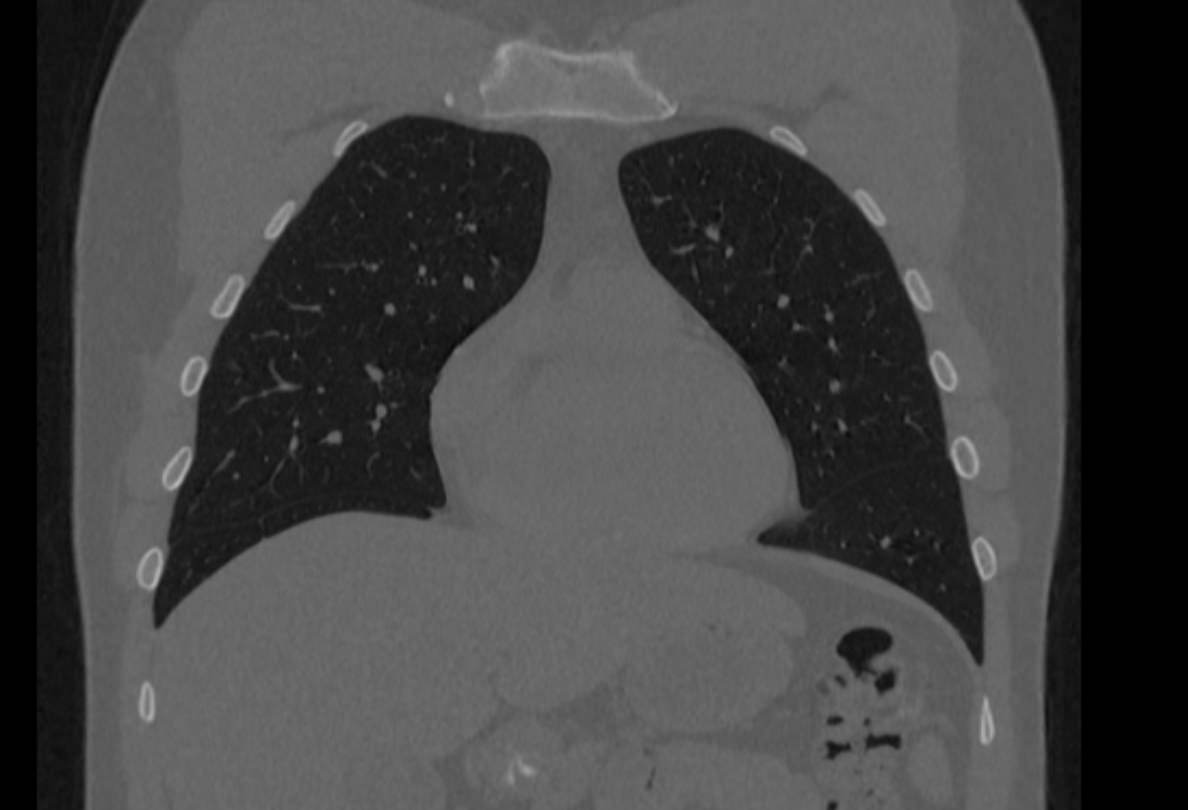

Мультиспиральная компьютерная томография ребер проводится в рамках протокола КТ органов грудной клетки. Грудина, ребра, грудной отдел позвоночника составляют костный каркас грудной клетки и при проведении КТ оценивается наличие деструктивных изменений в этих костных структурах.

КТ ребер является быстрым безболезненным высокоточным методом обследования костных структур грудной клетки. Метод позволяет получить детальные снимки и трехмерные цифровые изображения костно-мышечного каркаса грудной клетки. КТ широко используется в хирургии и травматологии при планировании оперативного вмешательства и в дальнейшем помогает оценить результаты проведенной операции.

Помимо этого, мультиспиральная КТ позволяет оценить состояние легких, трахеи, бронхов, изучить строение сердца и крупных сосудов, выявить патологию пищевода и лимфатических узлов средостения.